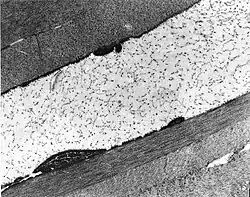

| The cornea is particularly opaque in the anterior stroma by slit-lamp biomicroscopy. | |

Congenital stromal corneal dystrophy (CSCD) is an extremely rare, autosomal dominant form of corneal dystrophy.[1] Only 4 families have been reported to have the disease by 2009.[2] The main features of the disease are numerous opaque flaky or feathery areas of clouding in the stroma that multiply with age and eventually preclude visibility of the endothelium. Strabismus or primary open angle glaucoma was noted in some of the patients. Thickness of the cornea stays the same, Descemet's membrane and endothelium are relatively unaffected, but the fibrils of collagen that constitute stromal lamellae are reduced in diameter and lamellae themselves are packed significantly more tightly.